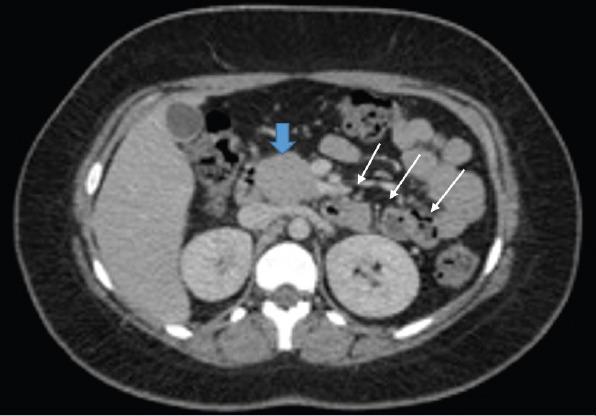

Agenesis of the dorsal pancreas (ADP) is extremely rare disease with no specific symptoms and there is no clear pathogenesis. Approximately half of the affected individuals develop diabetes resulting from reduced islet cell mass secondary to lack of endocrine structures. In this case, we aimed to present a 17-year-old female patient with ADP accompanied by a pancreatic cyst.

背侧胰腺发育不全(ADP)是一种极为罕见的疾病,没有特定症状,发病机制也不明确。大约一半的患者会因内分泌结构缺失导致胰岛细胞数量减少而患上糖尿病。在此病例中,我们旨在介绍一名17岁患有ADP并伴有胰腺囊肿的女性患者。